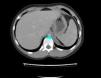

Presentamos el caso de un varón que, a las 22 semanas de gestación, es diagnosticado mediante ecografía prenatal de masa abdominal izquierda, que se confirma al nacimiento. El paciente es remitido a nuestras consultas para valoración y seguimiento durante el cual se solicita una angio-TC, que muestra la presencia de la lesión localizada en el interior del diafragma izquierdo (fig. 1), así como nuevo estudio ecográfico que pone de manifiesto la presencia de flujo dependiente de arteria esplénica (fig. 2), todo ello compatible con secuestro pulmonar. Dados los hallazgos radiológicos, se decide tratamiento quirúrgico. Durante la intervención, tras acceder al pilar diafragmático izquierdo, se localiza una formación de consistencia sólida, blanco-grisácea, cuyo aspecto macroscópico es compatible con tejido pulmonar. Se reseca de forma íntegra y se remite la pieza al servicio de Anatomía Patológica, que confirma el diagnóstico. Tras 6 meses de la intervención, el paciente permanece asintomático y sin secuelas.

La angio-TC es la prueba diagnóstica más adecuada en la detección de lesiones peridiafragmáticas6,7, ya que es una exploración no invasiva, rápida, de elevada resolución espacial y que permite obtener la máxima información sobre las relaciones anatómicas con el árbol bronquial y el parénquima pulmonar, siendo muy útiles los cortes coronales y oblicuos. Sin embargo, en nuestro caso, la TC logró una localización precisa de la lesión pero fue la ecografía Doppler la herramienta que permitió visualizar la vascularización proveniente de la circulación sistémica2. Este hecho fue decisivo, puesto que algunos autores consideran este hallazgo definitivo para el diagnóstico8. En un 66% de los casos, la vascularización anómala proviene de la aorta torácica baja o abdominal; sin embargo, hasta un 25% de los casos dependen de mamaria interna, subclavia, tronco celiaco, intercostales o arterias coronarias. En nuestro caso, el aporte sanguíneo se producía a través de arteria y vena esplénicas.